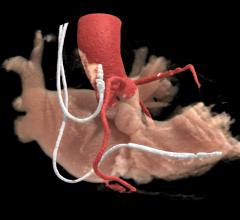

Feature | Computed Tomography (CT)

July 28, 2020 — The use of cardiovascular computed tomography angiography (CCTA) is one of the areas that has seen a…

There has been tremendous growth in the field of cardiovascular computed tomography (CT) in the past two decades, with…

July 20, 2020 – To meet the growing cardiovascular imaging needs of healthcare systems, Canon Medical Systems USA is…